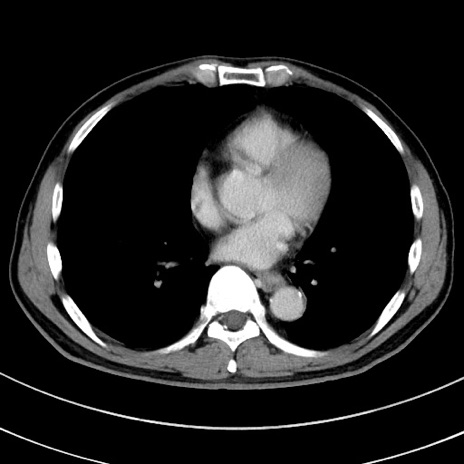

症例

冠状断像